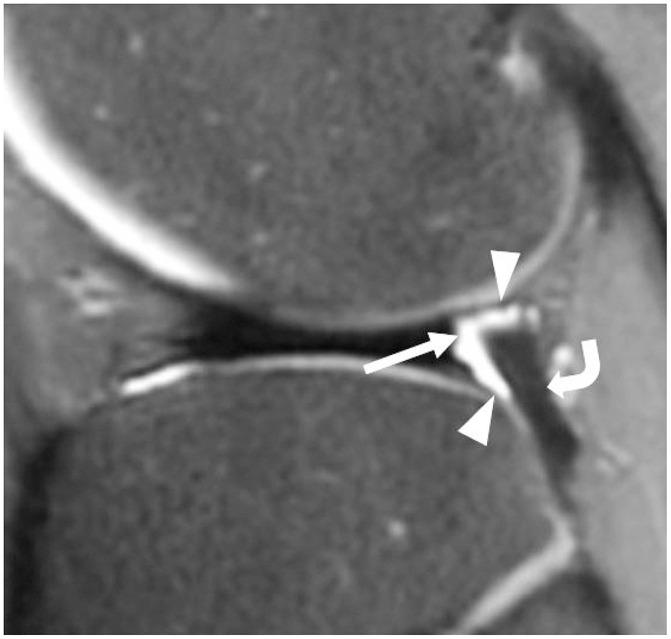

To accurately interpret knee MRI, it is important not only to know the basic meniscal anatomy but also to distinguish it from that under pathological conditions. Thus, it would be helpful to know the normal meniscus variants (false positives) that could be mistaken for meniscal tears, and tears that could easily be missed and incorrectly diagnosed as normal (false negatives). False positives include synovial recesses, meniscal flounce, the relationship between the popliteus tendon and lateral meniscus, transverse ligament, the anterior root of the meniscus, and meniscofemoral ligament. False negatives include focal radial tears, flap tears, posterior root tears, meniscocapsular separation, and discoid meniscal tears. In this pictorial essay, we reviewed the imaging data obtained in the aforementioned cases.